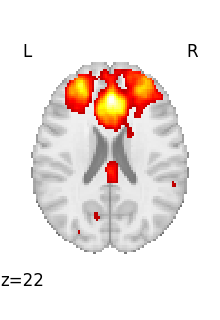

We can then plot it

<nilearn.plotting.displays._slicers.OrthoSlicer object at 0x7f3bc7cf1610>